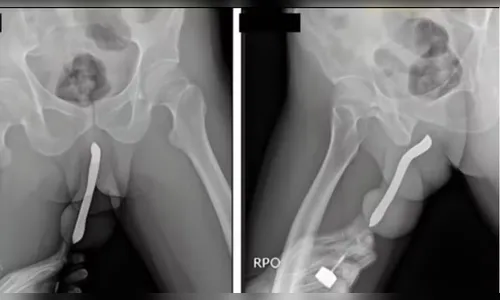

Um relatório baseado no banco de dados da Comissão de Segurança de Produtos de Consumo dos EUA (CPSC) revelou a lista de objetos inusitados retirados de órgãos genitais masculinos e femininos em prontos-socorros americanos. A análise, compilada pelo site Defector com dados referentes a 2024, aponta que itens como baterias, peças de jogos e até utensílios domésticos estão entre os corpos estranhos removidos por equipes médicas.

Embora motivada muitas vezes por curiosidade ou fetiche, a introdução de objetos inadequados no corpo é considerada uma prática de alto risco. Profissionais de saúde alertam que o hábito pode resultar em traumas físicos, infecções graves, perfurações e necessidade de intervenção cirúrgica de emergência.